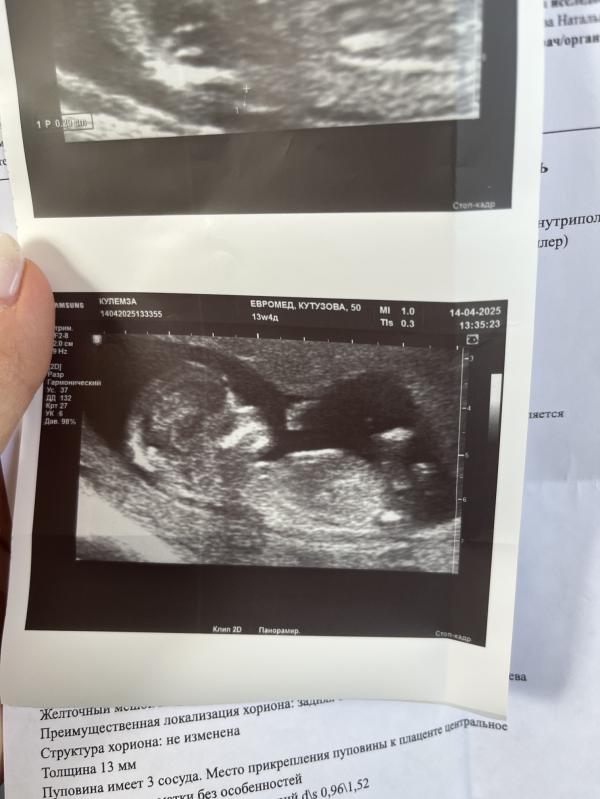

Господи, слава богу всё хорошо🤞🏻😍

Твп 2мм🙏

Ждём доченьку🩷🌸

14.04.2025